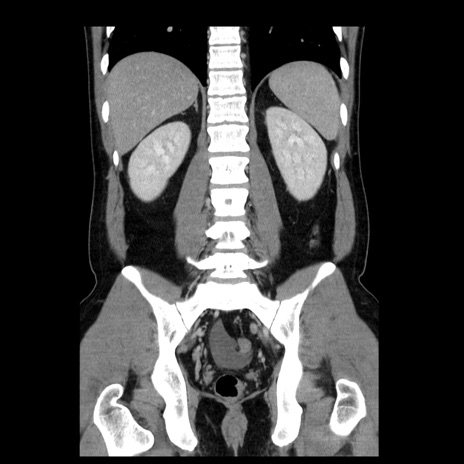

症例4(冠状断像)

【症例】30歳代男性

【主訴】腹痛、嘔吐

【現病歴】昨晩から突然の腹痛あり、その後嘔吐、軟便も出現。腹痛が改善しないため救急搬送となる。2日前にしめ鯖の食事歴あり。

【身体所見】意識清明、苦悶様、BP 135/90mmHg、BT 35.7℃、腹部:平坦、やや硬、心窩部〜臍部に自発痛、圧痛あり、筋性防御+、反跳痛-

【データ】WBC 8100、CRP 0.57